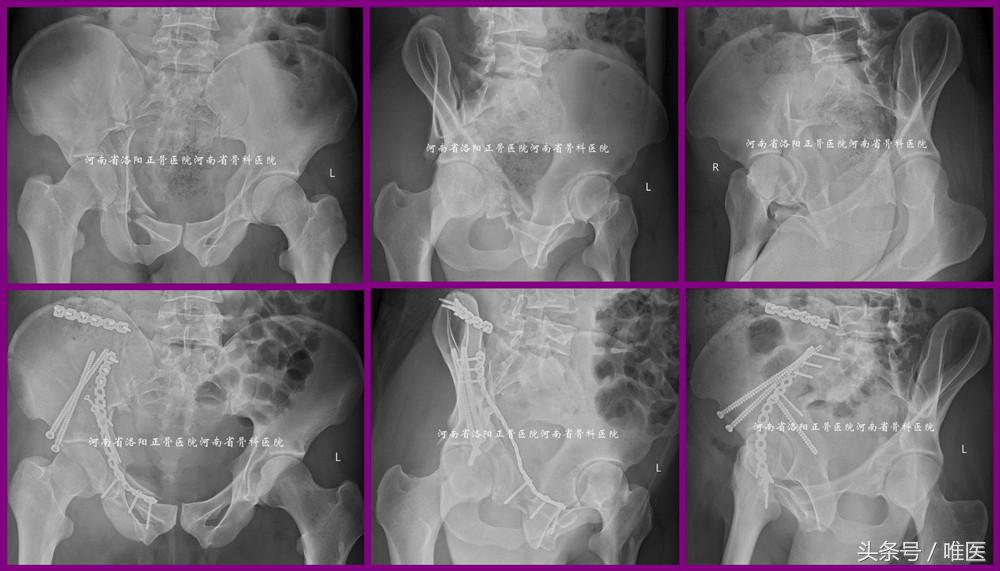

2. 用于治疗髋臼高位前柱骨折(即OTA-62A3.2)

病例2:一例61岁男性病人,以高处坠落致右髋部疼痛活动受限五天入院。入院诊断:右侧髋臼骨折(OTA-62A3.2)。入院后第三天手术。术后第一天坐起并逐渐拄双拐患侧下肢平足负重下床活动。术后第三天出院。术前及术后影像资料见图12。

图12. LC-II螺钉的经皮置入技术用于治疗髋臼高位前柱骨折(即OTA-62A3.2)。